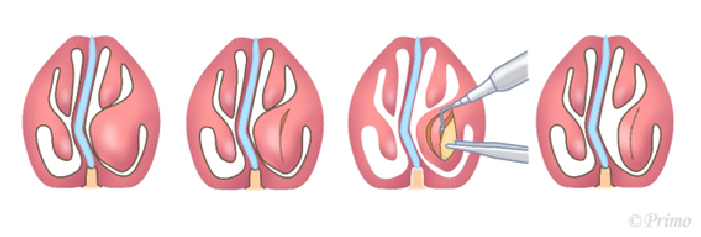

鼻翼軟骨(シルバーの部分)が鼻先の形体を形成します。

鼻翼軟骨の上部(水色の部分)を切除し、中央の赤い線で鼻翼軟骨を切断します。

切断した部分から上を反転させ、鼻先に突出させます。

先ほど切除した水色の部分の軟骨を、軟骨と軟骨の間に挟み込み、鼻の柱として用います(水色の部分)。

水色の部分のもう一枚を、鼻先の両サイドに固定し、鼻先を補強します(水色の部分)。この鼻翼軟骨移植法を行うことで、正面からもほっそりと、横からもシャープなかっこいい鼻先にすることがでます。